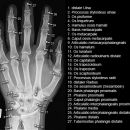

Handgelenk a.p.

Beurteilungskriterien

• Neigung der distalen Radiusgelenkfläche in der Frontalebene: 15 – 35°

• Längenverhältnis Radius – Ulna: Proc.styloideus radii überragt Gelenkfläche der Ulna um 9 –12mm (<9mm Ulna-Plusvariante, >12mm Ulnaminusvariante)

• Kontinuität der drei Karpalbögen:

Proximaler Bogen: proximale Gelenkflächenkonturen von Scaphoid, Lunatum und Triquetum

Mittlerer Bogen: distale Gelenkflächenkonturen von Sacphoid, Lunatum und Triquetum

Distaler Bogen: proximale Gelenkflächenkonturen von Capitatum und Hamatum

Fehlende Abgrenzbarkeit, Versatz oder Unterbrechung sind als pathologisch zu bewerten und deuten auf eine Luxation hin.

Trapezförmige Darstellung des Lunatum in Neutralstellung? Augenzeichen des Hamulus? Superposition von Pisiforme und Triquetum? Metacarpale III in Projektion innerhalb der Radiusgelenkfläche? Lunatum zu >50% über Radiusgelenkfläche? Cave: bei Radial- oder Ulnarduktion wandert das Lunatum in umgekehrter Richtung.

• M-förmiger Verlauf der Gelenkspalten der Carpometacarpalgelenke? Luxationsstellung in den Carpometacarpalgelenken (meist dorsale Luxation)?

• Gelenkspaltweiten des Radiocarpalgelenk 2 – 2,5mm, der Carpometacarpalgelenke 1 –2mm, distales Radioulnargelenk 2mm, Gelenksspaltweiten der Intercarpalgelenke 1,5 – 2mm

Cave: SL-Dissoziation (Ruptur des SL- Bandes, häufigste Gefügestörung): Terry-Thomas-Sign = SL-Spalt > 3mm, Siegelringzeichen = Ringförmige Transparenzminderung im mittleren Scaphoiddrittel durch orthograde Projektion der Taille infolge Rotation.

• Obliteration des Scaphoidfettstreifens?

• Täuschungsmöglichkeiten durch Vielzahl akzessorischer Ossikel (abgerundete, zirkulkär-geschlossene Kortikalis), geteilte Handwurzelknochen (Scaphoid, Lunatum, Pisiforme) und Gefäßkanälchen

• Target areas leicht zu übersehender Frakturen: distales Radioulnargelenk, Processus styloideus radii et ulnae, Basen der Metacarpalia (v.a. MCP I), Hamulus.

• Grundsätzlich gilt: unklare Verhältnisse ->CT-Indikation